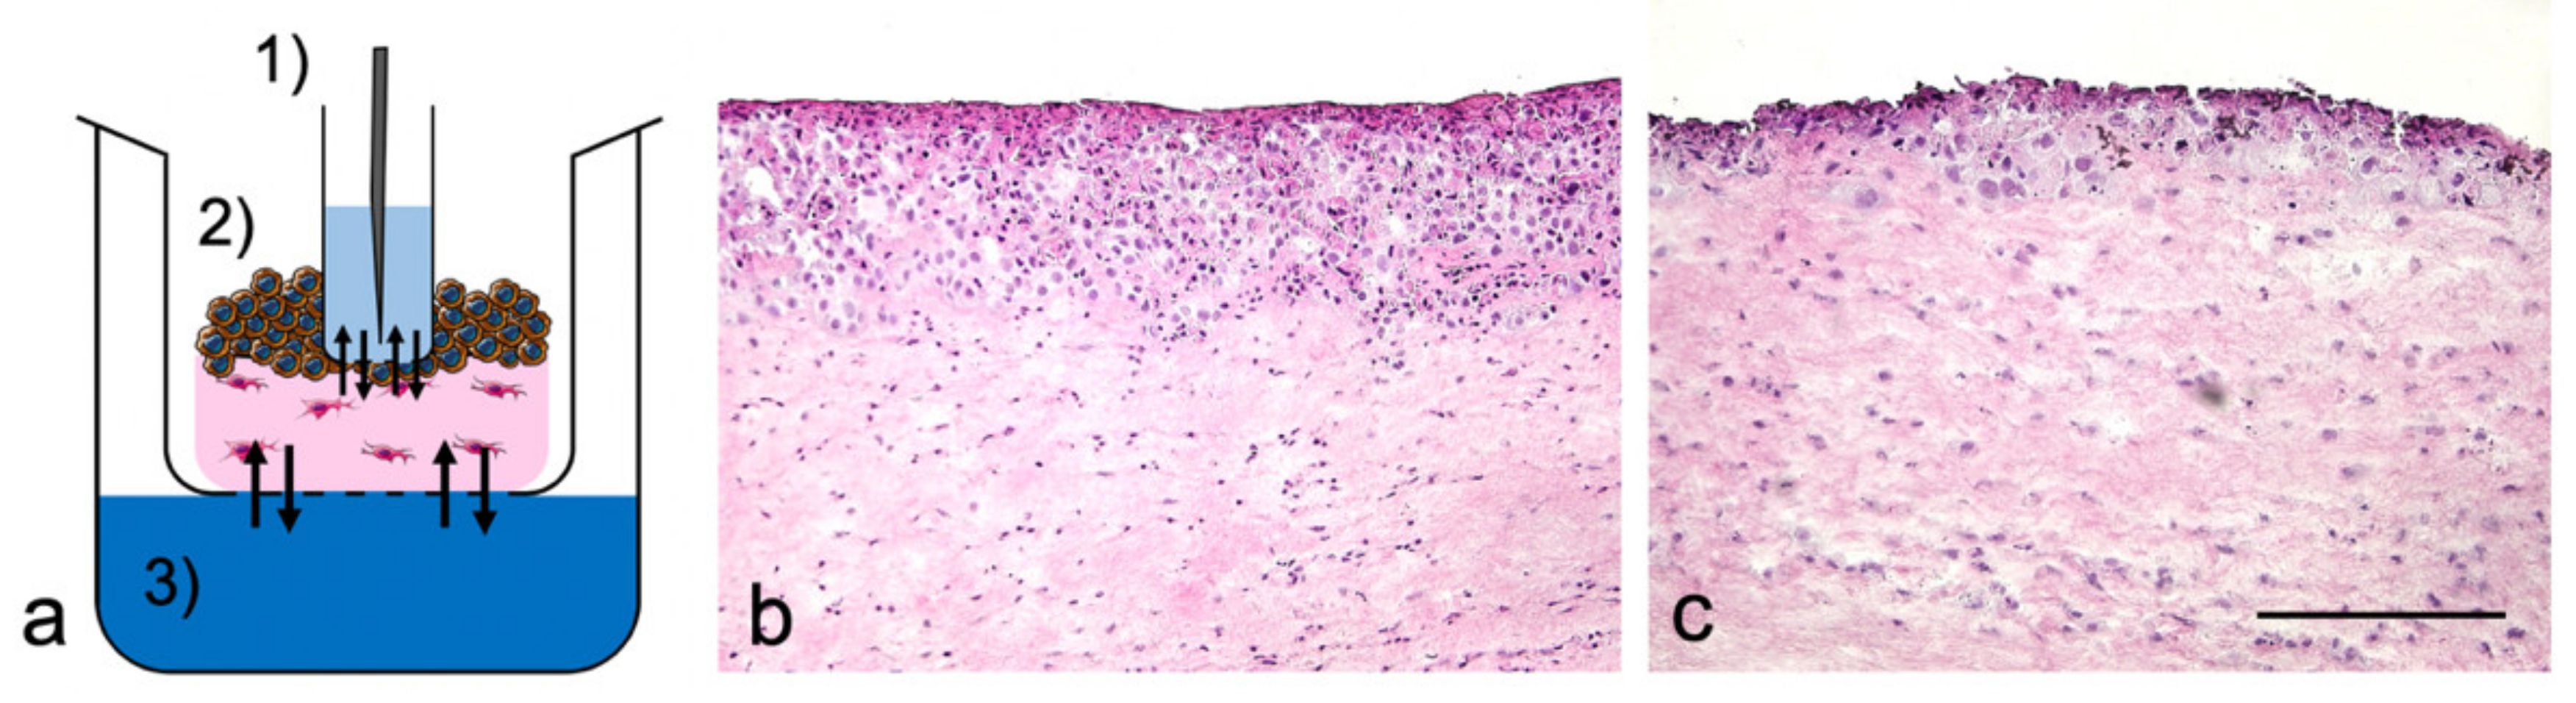

2.3. Sample Port Integration into Tumor Oral Mucosa (TOM) Models

Tumor oral mucosa (TOM) models were prepared as described elsewhere [14] but adopted to a 6-well-plate design to handle the integration of the sample port (Figure 1a). In brief, 0.3 × 106 oral fibroblasts were embedded in collagen G and 1 × 106 SCC-25 cells were seeded on top of these lamina propria equivalents one week after. The model growth medium was changed three times a week and replaced by model differentiation medium one week after seeding the tumor cells [14]. The sampling port was created by placing a 24-well insert (400 nm pore size) into the TOM model before the collagen started to solidify. The tumor cells proliferated and migrated into the collagen matrix around the sampling port for seven days, before docetaxel was applied. The 24-well insert was fixed by a custom-made metal support and filled with 600 µL serum-free growth medium. The top of the 6-well plate was sealed with aluminum foil (VWR, Darmstadt, Germany) instead of using the standard plastic lid. TOM models were incubated at 37 °C inside the autosampler of the UHPLC-MS/MS device (Agilent Technologies GmbH, Waldbronn, Germany) for the 96 h observation period in the final week of TOM model culture.

The TOM models reproducibly showed an unstructured and hyperproliferative epithelial layer with pleomorphic tumor cells, also separating from the epithelial layer into the lamina propria. Neither the sampling port nor the cultivation within the autosampler of the UHPLC-MS/MS device influenced the tumor growth. The effects of docetaxel on the tumor size in TOM models by supplementing the differentiation medium with either two drug doses or the vehicle control were determined. Whereas the vehicle control did not change the tumor morphology (Figure 1b), docetaxel caused a dose-dependent reduction of tumor size with abundant epithelial cell death (Figure 1c). The average tumor size declined from 347 ± 72 µm (untreated) to 100 ± 45 µm (max docetaxel concentration, n = 4 each).

Figure 1. Experimental design and morphology of tumor oral mucosa (TOM) models. (a) Schematic cross-section of (1) sampling port with the needle of the autosampler, (2) TOM model with tumor cells (brown) and fibroblasts (magenta) within lamina propria, (3) Reservoir with differentiation medium, supplemented with docetaxel. The arrows indicate drug diffusion equilibria. Hematoxylin and eosin (H&E) staining of TOM models following two applications of (b) the vehicle control and (c) 7000 ng/mL docetaxel. Images were representative of four batches; scale bar = 250 µm.